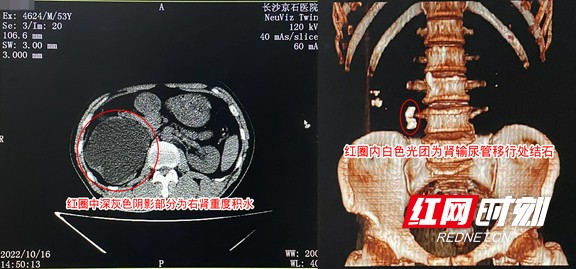

吴先生术前部分检查结果局部图。

10月16日,吴先生在长沙京石医院先接受了结石相关检查,确诊患有右肾肾盏多发性结石、右肾输尿管移行处结石,此处结石已达3厘米并造成该侧泌尿系统梗阻,并发右肾重度积水,急需手术解除梗阻,于是吴先生立即办理了入院手续,准备接受手术治疗。